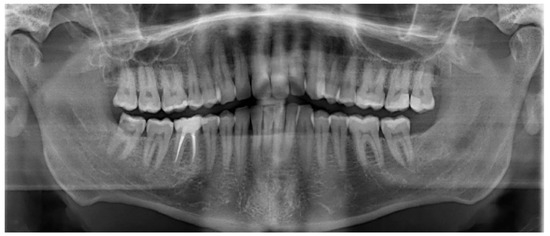

Globally, oral diseases pose a serious threat to public health because they affect people of all ages and place a heavy strain on healthcare systems. Oral potentially malignant disorders, oral cancer, autoimmune diseases, and various infections of the oral cavity are among these conditions. To avoid problems and enhance patient outcomes, oral disease diagnosis and care are crucial.

The field of oral illness detection and management has undergone a revolution due to the emergence of new technologies and diagnostic techniques. These developments have resulted in the discovery of new risk factors and biomarkers for oral disorders, enhanced imaging methods, and the creation of more efficient and individualised treatment modalities.